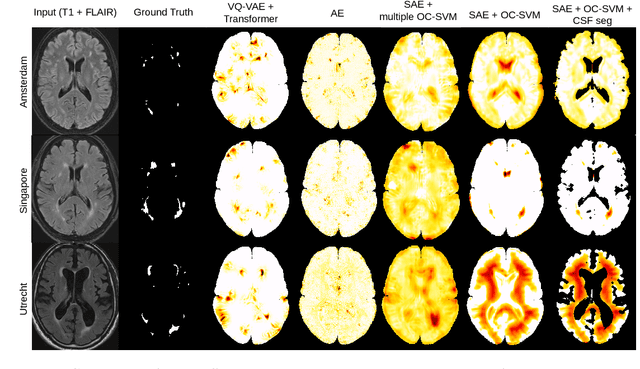

Abstract:Anomaly detection remains a challenging task in neuroimaging when little to no supervision is available and when lesions can be very small or with subtle contrast. Patch-based representation learning has shown powerful representation capacities when applied to industrial or medical imaging and outlier detection methods have been applied successfully to these images. In this work, we propose an unsupervised anomaly detection (UAD) method based on a latent space constructed by a siamese patch-based auto-encoder and perform the outlier detection with a One-Class SVM training paradigm tailored to the lesion detection task in multi-modality neuroimaging. We evaluate performances of this model on a public database, the White Matter Hyperintensities (WMH) challenge and show in par performance with the two best performing state-of-the-art methods reported so far.